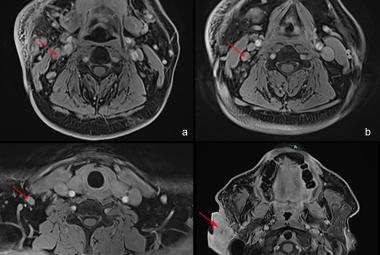

De Winter syndrome is a rare but important ST-elevation myocardial infarction (STEMI) equivalent, that is characterised by severe stenosis of the left anterior descending artery (LAD). It can be easily misdiagnosed due to its atypical electrocardiogram (ECG) pattern which causing a delay in reperfusion, hence increases risk of mortality. Herein, we reported a 38-year-old man presented to the emergency department (ED) with initial ECG showed hyperacute T wave, which later evolved to de Winter syndrome ECG pattern after serial ECG were done. He was immediately referred to the cardiology team and underwent immediate percutaneous coronary intervention (PCI) to revascularise the stenosis found at the left anterior descending artery (LAD). He showed good outcomes and no complication after the procedure. This paper aimed to shed light on the importance of early identification, right diagnosis and treatment in De Winter syndrome case to avoid complications.